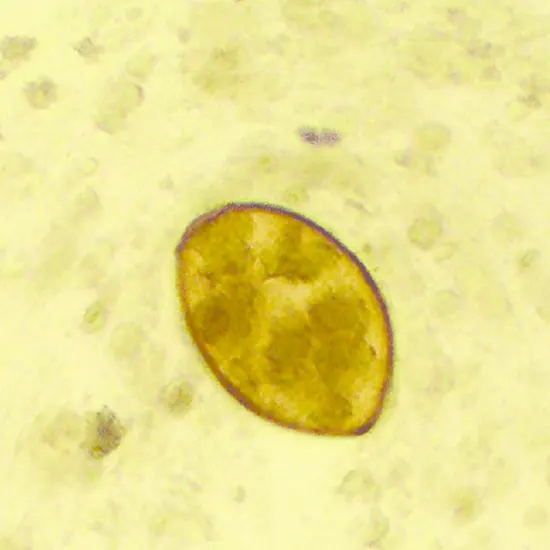

Following centrifugation, specimens of Paragonimus westermani are inspected under a microscope for eggs using the Formalin/Ethyl-Acetate Concentration Procedure.